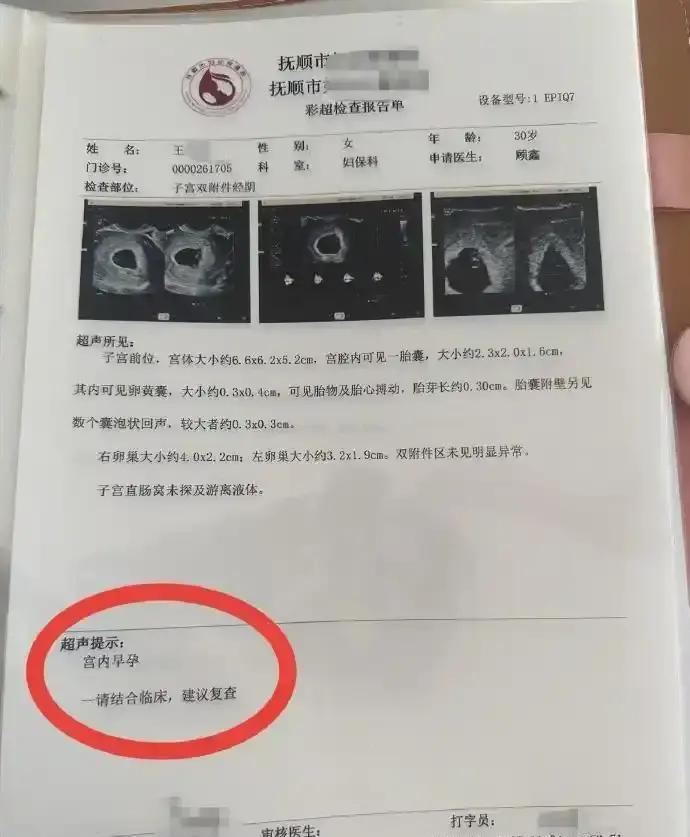

辽宁抚顺的一位准妈妈最近经历了人生中过山车般的时刻。怀孕16周的王女士,原本只是按部就班地进行产检,却在医院拿到了一份极其罕见的诊断报告。从去年11月到12月,短短一个月的时间里,她在医院进行了四次产检,每一次彩超单上的图像都在发生变化——最终确认,她怀上了四胞胎。 这并非普通的四胞胎。根据相关医生的诊断,王女士怀上的是同卵四胞胎。在医学领域,同卵四胞胎的发生率极低,属于非常罕见的个案。更复杂的情况在于,医生指出第四个胎儿为“无心畸胎”。这是一个专业性很强的术语,意味着这个胎儿虽然没有正常的心脏发育,但依然依赖其他胎儿的血液循环在母体内生存。这种特殊的医学状况,无疑给整个孕期增添了巨大的不确定性和风险。 对于普通家庭而言,多胞胎往往意味着双倍的喜悦,但在医学视角下,这更多代表着高风险妊娠。从数据来看,自然受孕情况下同卵四胞胎本就凤毛麟角,而伴随无心畸胎的情况更是让保胎之路布满荆棘。王女士在抚顺当地医院进行的这四次检查,实际上是一个不断排查和确认的过程。每一次彩超,不仅是在数胎儿的数量,更是在评估母体和每一个胎儿的生存质量。 网友们对此议论纷纷,有人感叹生命的奇妙与不易,也有人为即将到来的抚养压力感到担忧。毕竟,四个孩子的降生,对家庭的经济状况、父母的精力都是极大的考验。目前摆在王女士和家人面前的,不仅是喜悦,还有如何根据医生的专业建议,制定最科学、最安全的后续妊娠方案。 这起事件也给广大备孕及孕期女性提了个醒:规范的产检流程至关重要。像王女士这样,通过连续、定期的超声检查,才能及时发现多胎妊娠及胎儿发育异常等特殊情况。面对罕见病例,医学干预和监测是保障母婴安全的最有效手段。祝愿这位准妈妈能平安度过接下来的孕期,也希望这个小生命群体能在现代医学的保驾护航下,迎来最好的结局。 以上内容仅供参考和借鉴